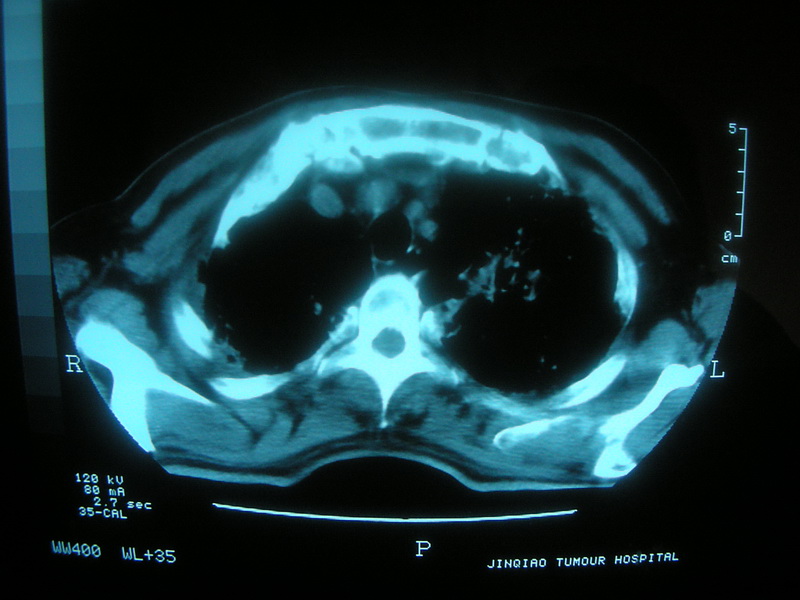

标题: CT11692:男,63岁,糖尿病史15年.抗炎治疗7天,病情 [打印本页]

标题: CT11692:男,63岁,糖尿病史15年.抗炎治疗7天,病情

请老师看看是结核还是炎症?

根据影像表现及临床符合结核感染。

双肺继发性肺结核伴感染!

糖尿病首先考虑结核并感染。